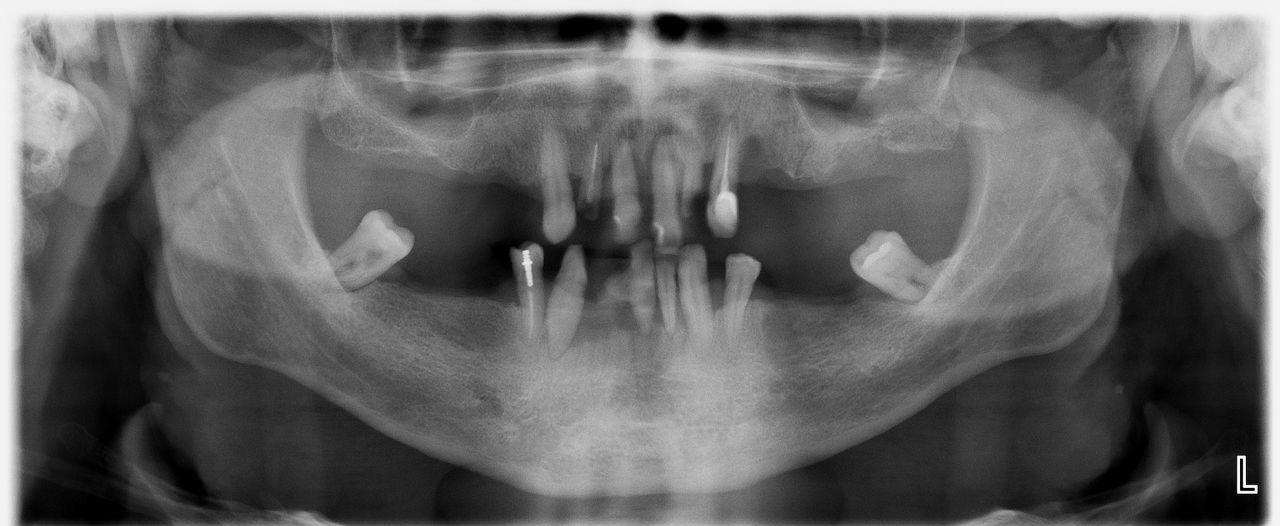

Случай 2: Лечение с импланти